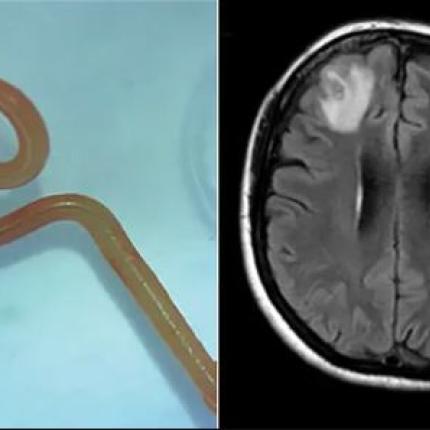

Η ασθενής υπέφερε από κατάθλιψη και προβλήματα μνήμης